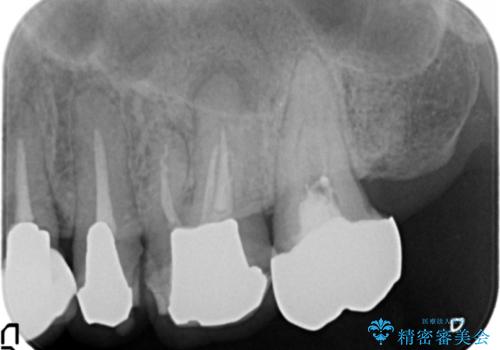

- 左側の奥歯で噛むと痛みや違和感が強く、しっかり噛めない、治療したいと希望され来院されました。

歯周組織検査やX線検査等、精査を行った結果、根尖性歯周炎や不適合なクラウンによる歯茎の炎症、歯の破折等様々な問題が認められました。

根まで破折してしまっている歯は、残すことができないので抜去を行いインプラント治療、

残すことのできる歯は根管治療を行い、精密なセラミック治療を行うこととしました。